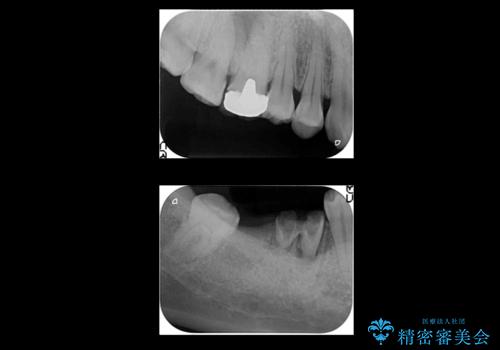

右上に部分矯正を行い、クリアランスを確保した後、右下にイプラントを2本埋入しています。

- およそ150万円 部分矯正30万円、インプラント治療37万円×2本、右上7emaxインレー、右上6 専門医による再根管治療およびジルコニアクラウン26万円費用は治療当時の料金となります

上の歯が伸びだしてきていたため、部分矯正を行い歯を移動させてから、向かい合わせの歯にインプラント治療を行っています。